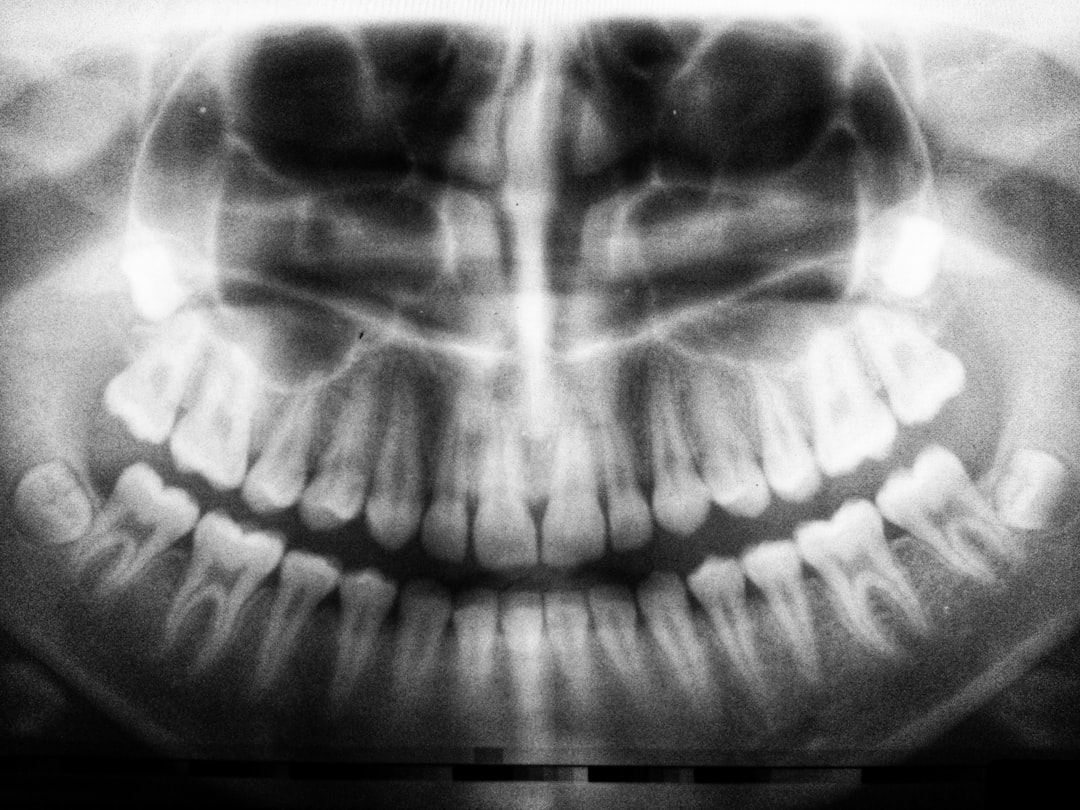

치아 오버레이를 받는 과정은 여러 단계로 나뉘어져 있습니다. 첫 단계는 꼼꼼한 진단입니다. 치과의사는 환자의 치아 상태를 정밀하게 검사하고, 필요한 경우 사진을 찍습니다. 그런 다음, 치아의 형태와 색깔을 결정하기 위한 상담이 이뤄집니다. 이 과정이 중요한 이유는 오버레이의 재료와 디자인이 환자의 특성에 따라 달라질 수 있기 때문인데요, 그야말로 맞춤형 접근이죠. 다치거나 변형된 치아를 교정하기 위해 어느 정도의 준비가 필요한지도 상세히 논의합니다. 다음 단계에서 직접 치아에 오버레이를 붙이는데 이때 시술자는 치아를 정리하고 표면을 매끄럽게 한 후, 접착제를 이용해 오버레이를 붙입니다. 그 과정에서 환자도 충분히 편안하도록 배려해 주기 때문에, 치료가 상당히 쾌적하게 이루어집니다.